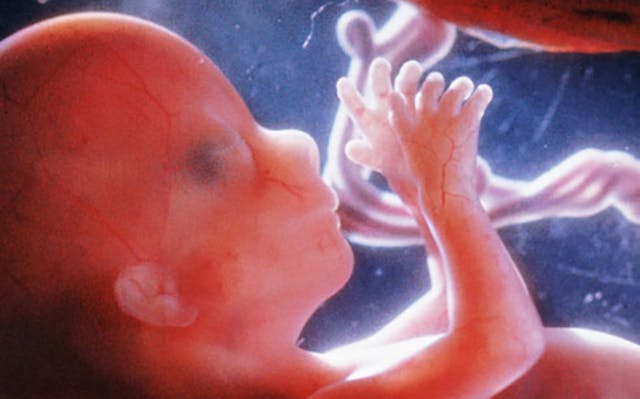

It really is mind-blowing to learn about the development of preborn children. According to the Endowment for Human Development, which released a prenatal video series in partnership with National Geographic, by nine weeks after fertilization (according to six different studies), “the nerve receptors in the face, palms of the hands, and soles of the feet can sense and respond to light touch. Following a light touch on the sole of the foot, the fetus will bend the hip and knee and may curl the toes.” Between 12 and 13 weeks after fertilization (according to three different studies), the preborn child’s “whole body surface, except the top of the head and the back, responds to light touch.” By 24 weeks in the second trimester, the preborn baby “responds to pressure, movement, pain, hot and cold, taste, and light.”

Yes, even while still in the womb, babies can feel temperature changes.

These babies not only feel pain, but so much more. They sense even soft touch, taste, light, and temperature. They are human beings, just like the rest of us, and they should have the right to continue to live and grow.